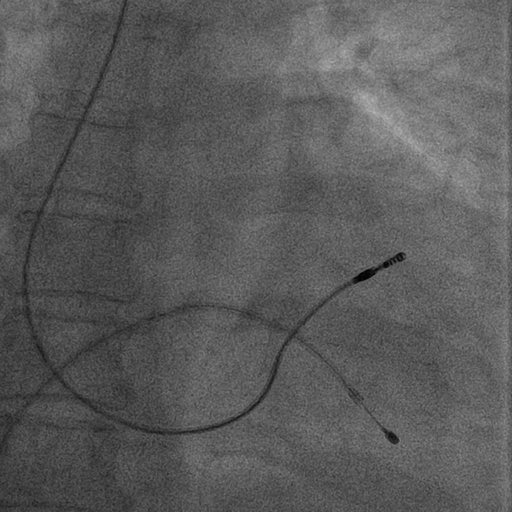

RVOT pacing

• Active fixation lead

• Stylet shaping

Mond curve

mond_curve.jpg

rvot_before_screw.jpg

rvot_lead.jpg